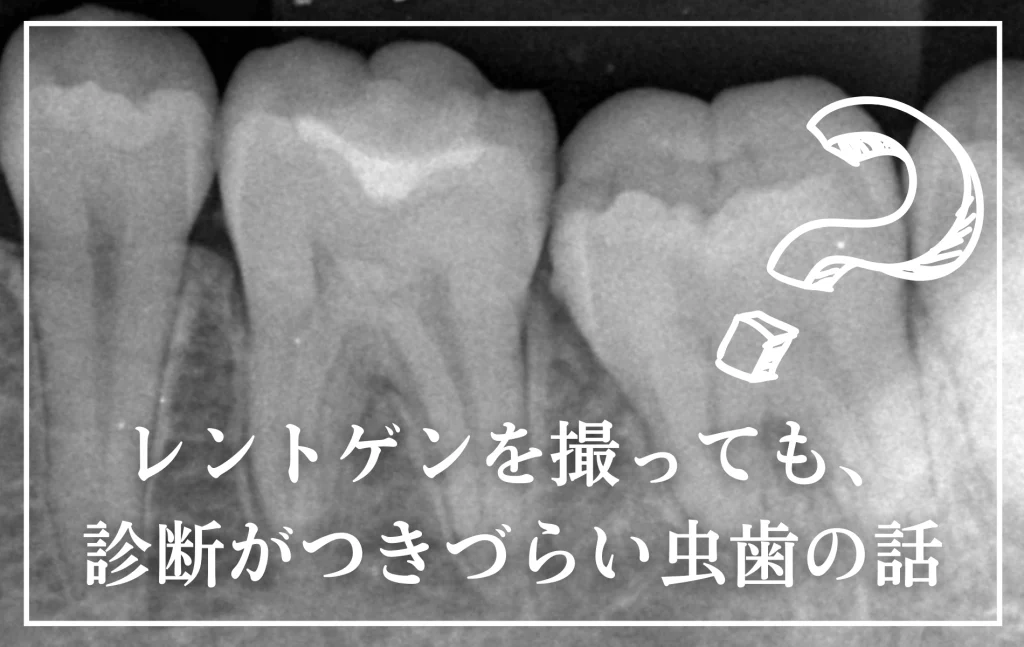

レントゲンを撮っても、診断がつきづらい虫歯の話

しかし、レントゲン写真という“窓”からでは、どうしても見えにくい、あるいは捉えきれない虫歯が存在します。

ここでは、患者さんの目線で、レントゲン写真について、レントゲン写真に写りにくい虫歯の種類、その見つけ方、予防できる対策、実際の治療例をご紹介し、掘り下げていきます。

実は「レントゲンで見えない虫歯」もある

上記のように、虫歯の診断の第一選択といえるレントゲン写真ですが、レントゲン写真で全ての虫歯が診断できるかというと、そうとも限りません。

虫歯の中には、レントゲン写真に写りにくい物も存在するのです。

上記のような理由から、レントゲン写真から大きい虫歯と診断して治療してみると、そうでもなかったり、小さな虫歯と思っていざ治療してみると、かなり進行していて驚くこともあります。

同じクリニックで同じ機械を使って診断をしていても、担当する先生によって診断される虫歯の数が違ったりする事もあります。